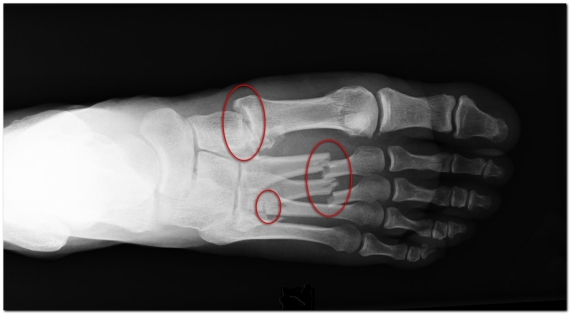

Диагностика

При диагностике перелома плюсневых костей учитываются анамнез (наличие травмы), жалобы пациента, результаты объективного осмотра стопы и данные рентгенологического исследования.

-

Анамнез. Стрессовые переломы пятой плюсневой кости у пострадавших возникают в результате резкого увеличения физической активности на стопу.

Жалобы пациента. У некоторых людей, занимающихся спортом на регулярной основе, наблюдаются жалобы на боль в области стопы, которая проявляется исключительно при нагрузке. Со временем симптомы усиливаются, и у пациента формируется яркая клиническая картина «свежего» перелома.

Объективное обследование. В процессе клинического осмотра врач-травматолог обязан провести пальпацию обеих лодыжек, ладьевидной кости и основания пятой плюсневой кости.

Рентгенологическое обследование. При наличии подозрений на перелом пятой плюсневой кости выполняется рентгенография стопы в трех проекциях: переднезадней, боковой и косой.

В наиболее сложных случаях могут быть использованы иные методы лучевой диагностики, такие как МРТ или сцинтиграфия с технецием.